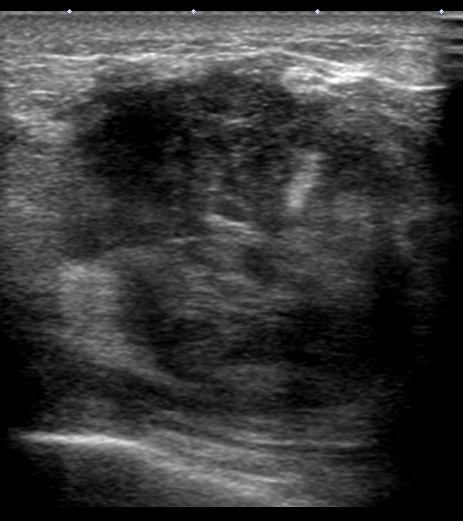

エコーで見ると…

裏側の筋層(大胸筋)とは接してはいるけど、浸潤しているのか?は不明

このようにする(した)のです。

このように、腫瘍から遠い部位は大胸筋から剥がしていって、腫瘍から近づいた地点から大胸筋も一緒に切除していくのです。

大胸筋は全切除する必要は無論なく、腫瘍の真裏(腫瘍床といいます)及びその周辺部分のみ合併切除するのです。

摘出した後にひっくり返すと、腫瘍床には大胸筋が一緒に切除されている様子が解りますね。

⑥いよいよ!(腫瘍を含んだ)乳腺を大胸筋から外す

今回は、この操作の際に「腫瘍が(顕微鏡レベルでも)露出しないように」大胸筋を綺麗に合併切除したわけです。